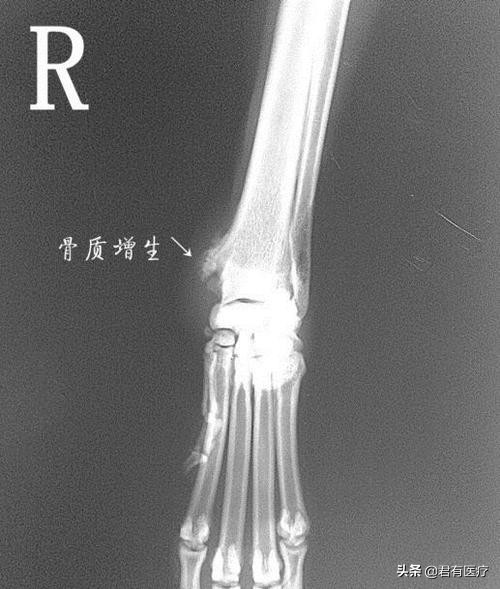

"骨刺"也叫骨质增生、骨赘,西医没有"骨刺"一说,规范叫法是"骨疣"。骨刺像脸会长皱纹、人体会衰老一样,是一种自然的老化现象,并不是疾病。

实际上,骨刺的形状并不像"刺",而是光滑的、鳞片状的,也不会"扎"到肉里,多数骨刺没有症状。

为避免骨与骨直接磨损,肌体代偿机制促使骨关节边缘增生,以保护关节。从这个角度上来讲,可以说,骨刺是骨骼的修理工。

通过骨质增生(骨刺)增加骨骼表面积,减少单位面积上的压力,使关节更加稳定。

与之对应的是,骨刺主要长在负重大、使用频繁的关节部位,如颈椎、腰椎、膝盖、脚跟等,这从另一面验证了上述理论。